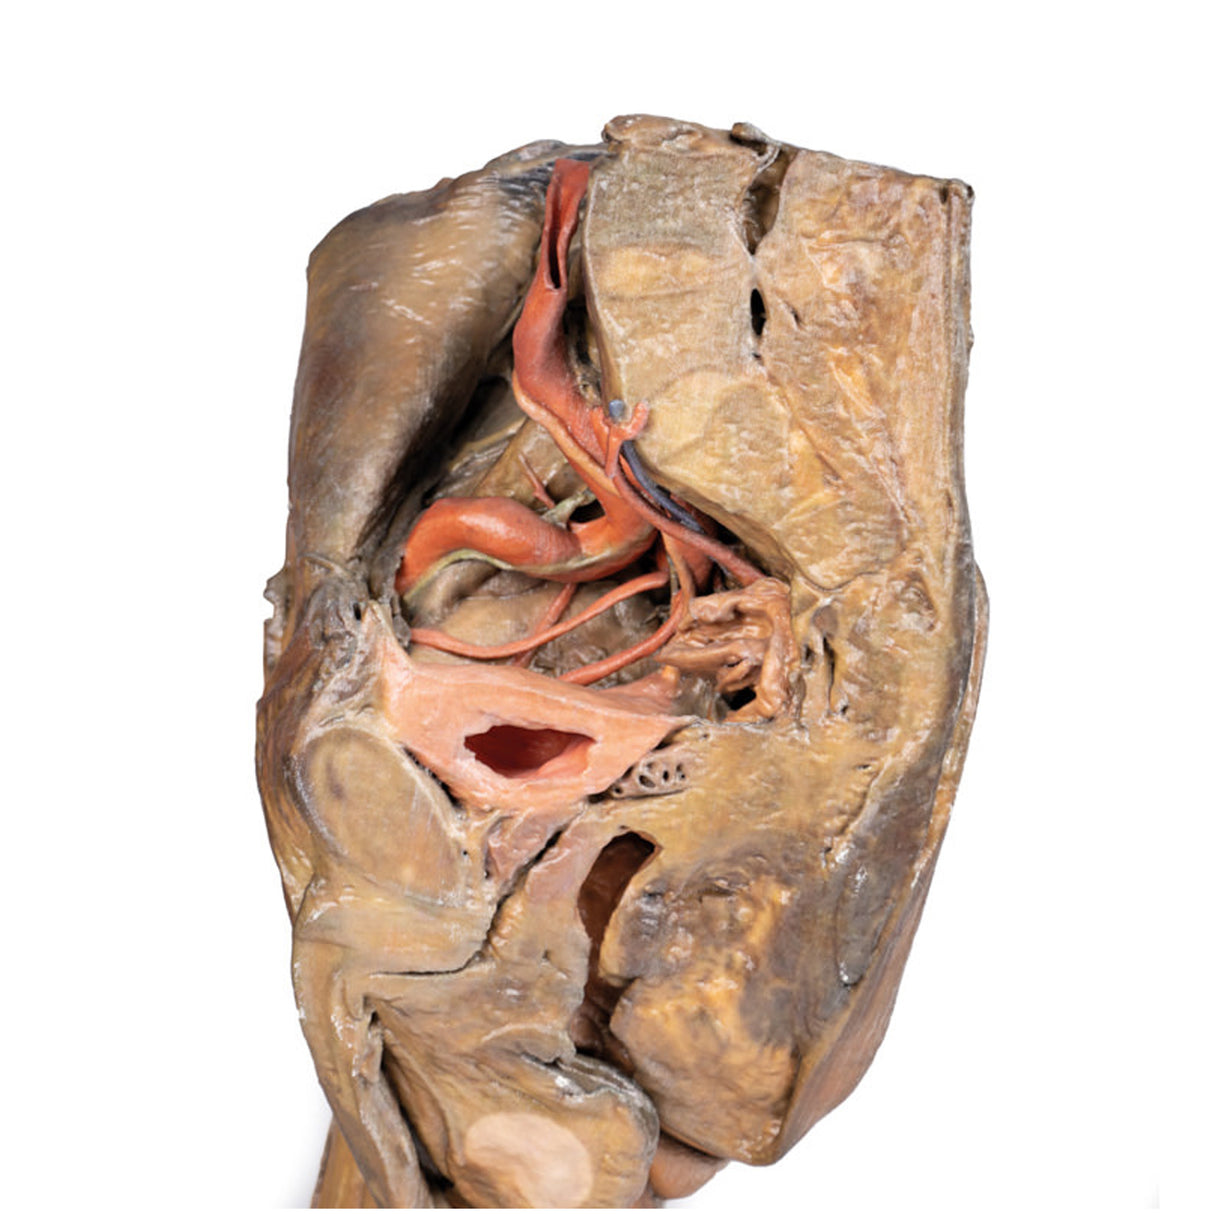

Male hemipelvis and thigh

Male hemipelvis and thigh

This 3D model preserves a right male pelvis sectioned just superior to the L5 vertebra and sectioned at the midsagittal plane, with the thigh preserved to near the midshaft of the femur.

The common iliac artery is preserved with several key branches visible, particularly the distribution of the internal iliac within the true pelvis. Several major vessels including the obturator artery and the partially obliterated umbilical artery passes towards the anterior abdominal wall (to form the medial umbilical ligament) and gives off the superior vesicle artery; while the roots of the iliolumbar, superior gluteal, inferior gluteal and internal pudendal artery are visible lateral to the urinary bladder. The ureter descends superficial to these vessels to approach the urinary bladder which is covered with peritoneum in this model.

The ductus deferens is exposed from the entry into the space via the deep inguinal ring and passing posteriorly (though sectioned from its normal insertion pathway and resting on the internal iliac artery). Adjacent to the ureter and on the superficial surface of the psoas major muscle is an enlarged iliac lymph node and part of the lymphatic vasculature ascending along the external iliac artery. The majority of the pelvis has been left undissected, allowing for an appreciation of the rectovesicular pouch and the exposed superior rectal artery and vein approaching the preserved portion of rectum. In cross section, the rectum, seminal vesicle and prostate are visible (the section plane preserves parts of both the prostatic urethra and ejaculatory duct).

In the anterior thigh the borders and contents of the femoral triangle are well-preserved, with partial coverage by the flap of the anterior abdominal wall. Posteriorly the skin over the gluteal region and the gluteus maximus muscle have been removed as sequential windows to expose the gluteus medius and minimum muscles, the piriformis, the obturator internus with gemelli muscles, and the quadratus femoris muscle. The superior and inferior gluteal arteries are maintained superior and inferior to the piriformis, respectively; with the sciatic nerve exiting inferior to piriformis before passing deep to the retained portion of the gluteus maximus.